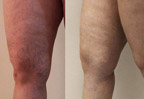

Фотографии До и После

Спасенные конечности

До и После